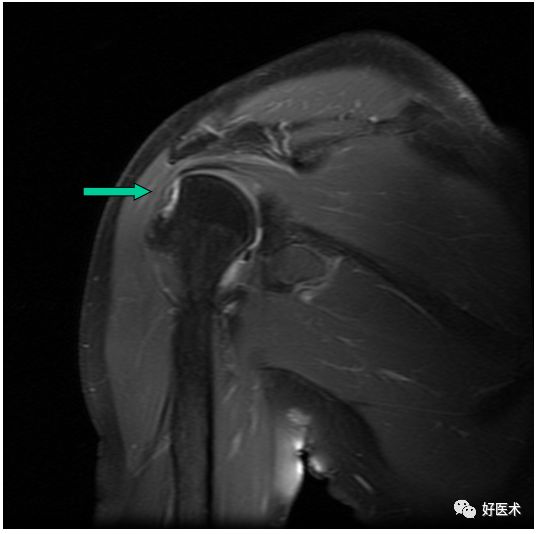

MR间接关节造影1.5T冠状面T1W脂肪抑制